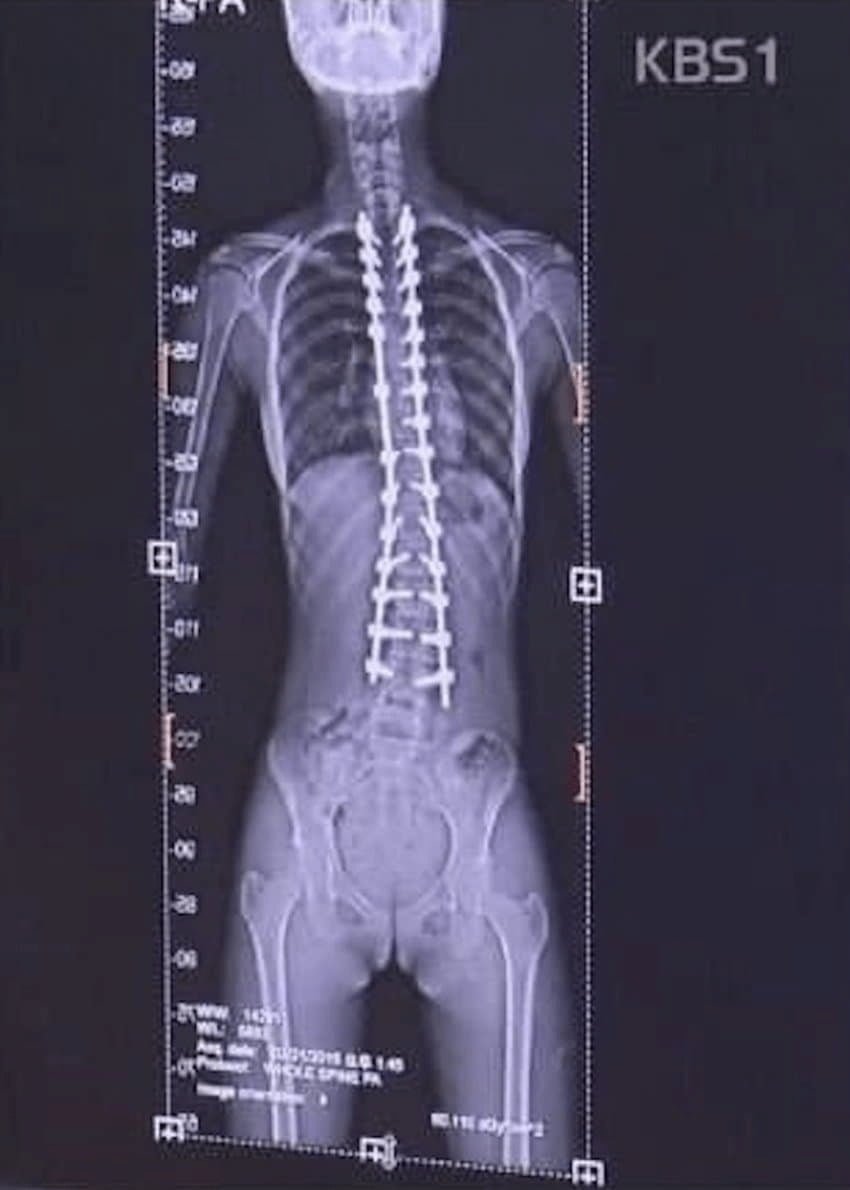

한 고등학생이 척추측만증으로 괴로워하며 응급실을 자주 드나드는 충격적인 실화가 공개되었다. 17세의 한지민은 심각한 병세 때문에 여러 번의 병원 방문을 피할 수 없었다. 엑스레이 검사 결과, 그녀의 척추는 심각하게 휘어 있었고, 수술이 불가피하다는 의사의 진단을 받았다.

이들은 단순히 척추가 옆으로 휘는 현상에 그치지 않고, 전체적인 회전까지 동반하여 장기들도 변형될 수 있다는 경고를 받고 있다. 이러한 상황을 앞두고, 그들의 가족은 어떻게 감당해야 할지를 고민하고 있으며, 이들 자매의 운명을 지켜보는 모두에게 경각심을 불러일으키는 사건이 되었다. 측만증의 비밀이 밝혀지길 바라며, 이 가족의 이야기가 더 많은 이들에게 알려져 이들이 희망을 찾을 수 있기를 기원한다.